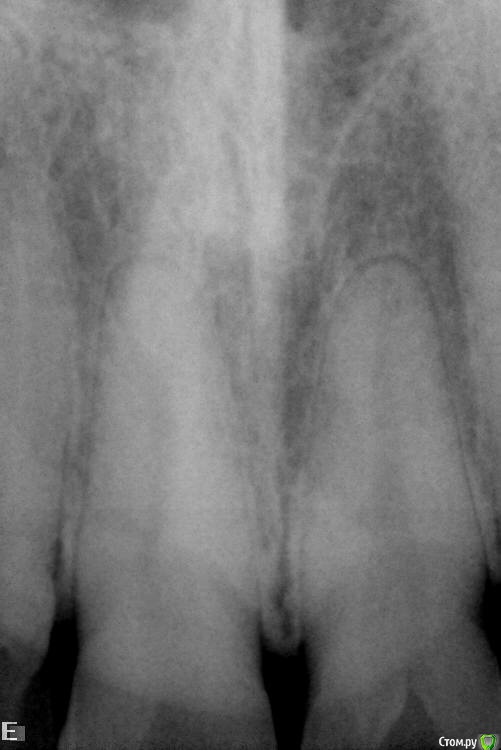

VladV Опубликовано 19 апреля, 2015 Поделиться Опубликовано 19 апреля, 2015 Помогите, пожалуйста, советом. Заранее извиняюсь за простыню. Около полутора месяцев назад пропустил два удара в голову. Один пришелся в верхнюю челюсть, другой в районе правой брови. Была сильно разбита верхняя губа, которая слиплась и срослась сама (не зашивали). Зубы, вроде бы, не беспокоили. Проверял холодом - реакция есть. Явных болевых ощущений не было, но как-то стал чувствовать верхнюю единицу (11), иногда совсем чуть-чуть зуб поднывал и было ощущение, что совсем немного сдвинулся назад, внутрь рта (возможно, всегда таким был, не обращал внимания). При смыкании зубов поверхностью верхнего к поверхности нижнего, а не нижний за верхний, явной боли не было, но я старался не смыкать лишний раз и не кусать этими зубами. Губа зажила где-то через две недели, только внутри уплотнение небольшое осталось. Не знаю, важно ли, но примерно после заживления губы то ли словил вирус, то ли есть связь с зубами, но начался сильный насморк, который длился недели две и вторая неделя была с густыми зелеными (простите за подробности) выделениями и даже иногда кровь шла из носа от попыток их вымыть и высморкать.Спустя месяц, когда насморк прошел, решил сходить к стоматологу в частную клинику и проверить зубы на всякий случай, т.к. непонятные ощущения в 11 зубе остались. Простучали зубы 22-21-11-12. У всех зубов чувствительность одинаковая, у 11 чуть сильнее. Сделали несколько прицельных снимков. Врач ничего криминального с корнями не обнаружил. Посоветовали сделать чистку зубов ультразвуком и AirFlow, т.к. был сильный налет и отложение камня.Через пару дней сделал чистку. Полтора часа чистили все зубы, так как около 5 лет до этого не чистил. Врач долго не мог понять, что за смолянистый темный налет был на зубах (не курю и кофем не злоупотребляю), в итоге выяснили, что из-за постоянного полоскания ротовыми ополаскивателями, содержащими хлор. Увлекался ими последние полгода. После травмы зуба казалось, что после ополаскивания зубу легче становилось и его долго ничего не беспокоило. Во время осмотра между верхними единицами обнаружился легкий кариес. Врач сказал, что на корни и мои ощущения 11 зуба он никак влиять не может. После чистки местами были травмированы десны, местами маленькие гематомы были, некоторые зубы стали особенно чувствительно переносить холодное и горячее. Но то ли так совпало, то ли из-за чистки, 11 зуб стал чаще поднывать, причем, непонятные ощущения переместились ближе к пространству между 11 и 12 зубом, и на 12 зуб вроде бы тоже стали распространяться. Сложно описать, но такое ощущение, что чувствительность куда-то ближе к носу ушла, иногда как будто напряжение какое-то между зубами возникало, будто еда застряла. Стал непроизвольно тсыкать - прислонять язык к щели 11-12, 11-21, 12-13 и втягивать резко воздух, так легче что ли становилось или из-за ощущений от увеличенных просветов между зубами. Потом то ли из-за того, что не пользуюсь передними зубами, то ли из-за чего-то другого, но появилось ощущение, что изменился прикус. Нижние единицы стали как-то ощутимее упираться в верхние единицы, будто в другом месте из-за якобы ушедшей чуть-чуть вперед нижней челюсти. Иногда верхние единицы становились как чужие, снижалась чувствительность что ли. Иногда кажется соленоватый привкус у десны между 11 и 12 зубами, хотя крови и каких-либо выделений в слюне нет. В какие-то дни эти ощущения уходили, в какие-то возвращались. Заметил, что у 11 зуба есть небольшая подвижность, определил прислоняя палец к щели 11-12 и сжимая/расслабляя челюсти. Понаблюдав неделю пошел уже в другую частную клинику. Там опять сделали снимки (прилагаю к сообщению), опять ничего криминального не обнаружили. Кариес легкий между 11 и 21 видят, рекомендуют убрать и отреставрировать зубы, но не видят связи с моими ощущениями. Сказали, наблюдать дальше за зубом, сделать контрольные снимки месяца через три и не заморачиваться. Легко им говорить, у меня уже паранойя развиваться начала. Каждое утро просыпаюсь и сразу прислушиваюсь к ощущениям, потом весь день то отвлекаешься, то опять вспоминаешь и тсыкаешь. Все еще осложняется тем, что в двадцатых числах я почти на 20 дней улетаю в Египет, где если и случится чего, то вряд ли смогут квалифицированно помочь с зубами.В итоге решил поискать информацию в Интернете и наткнулся на этот форум. Начитался ужасов всяких и еще больше теперь боюсь уезжать. Правда, непонятные ощущения после этого стали реже возвращаться, уже пару дней, испугались, наверно. Записался на панорамный снимок, который и прикладываю. Прошу специалистов высказать свое мнение. Действительно ли забить и жить с этими непонятными ощущениями или дальше копать. Какие препараты лучше взять на случай, если что-то пойдет не так в поездке? Заранее спасибо за рекомендации и еще раз простите за простыню. Ссылка на комментарий